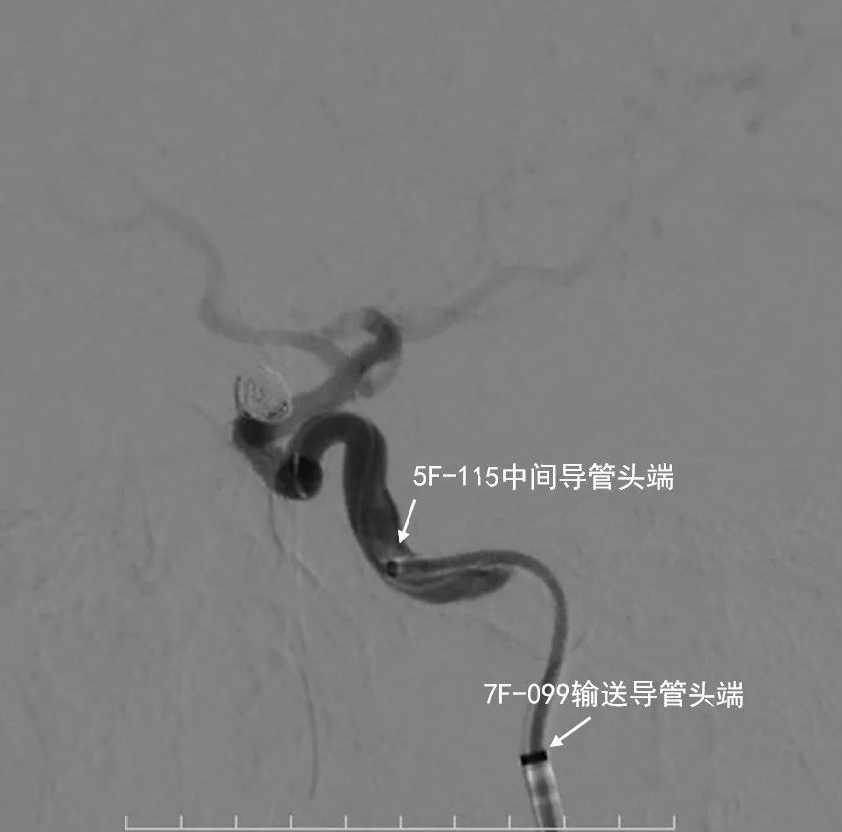

- 5F 115cm颅内支持导管在泥鳅导丝支撑下超选入右侧颈内动脉C3段内。支架微导管先经5F颅内支持导管在微导丝支撑下超选入右侧大脑中动脉M1段。后微导管塑形后经深瑞达7F 90cm输送导管在微导丝支撑下超选入动脉瘤腔内。

动脉长鞘怎么置入深谋远路 | 千人皆翘首,万唤今始来——国内首款7F长鞘在血流导向密网支架联合弹簧圈栓塞治疗动脉瘤的首次应用_https://www.jmylbn.com_新闻资讯_第25张

微导管后撤弹入瘤腔